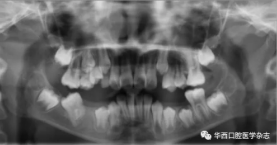

全景片及錐形束CT(cone beam computed tomo-graphy,CBCT)三維重建影像顯示:46牙胚存在,牙冠朝向遠中,且牙長軸與下頜骨下緣接近平行,遠中根發育約為根長2/3,近中根發育約為根長1/2且稍向下彎曲,近中根與45牙關系密切,下頜其余牙胚正常(圖2、圖3)。